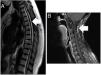

ResultsThe mean follow-up period was 27 months. No patient developed a post-operative cerebrospinal fluid (CSF) dural-cutaneous fistula. CSF leakage was not observed in the control MRIs at 6 weeks.

ConclusionsWe describe, for the first time, the use of this type of U-clip with a flat inner side. The non-penetrating titanium U-clip facilitates effective and rapid dural closure at all spinal levels due to its flat internal face when closed. The U-clips did not cause significant artefacts or distortions on the magnetic resonance imaging.